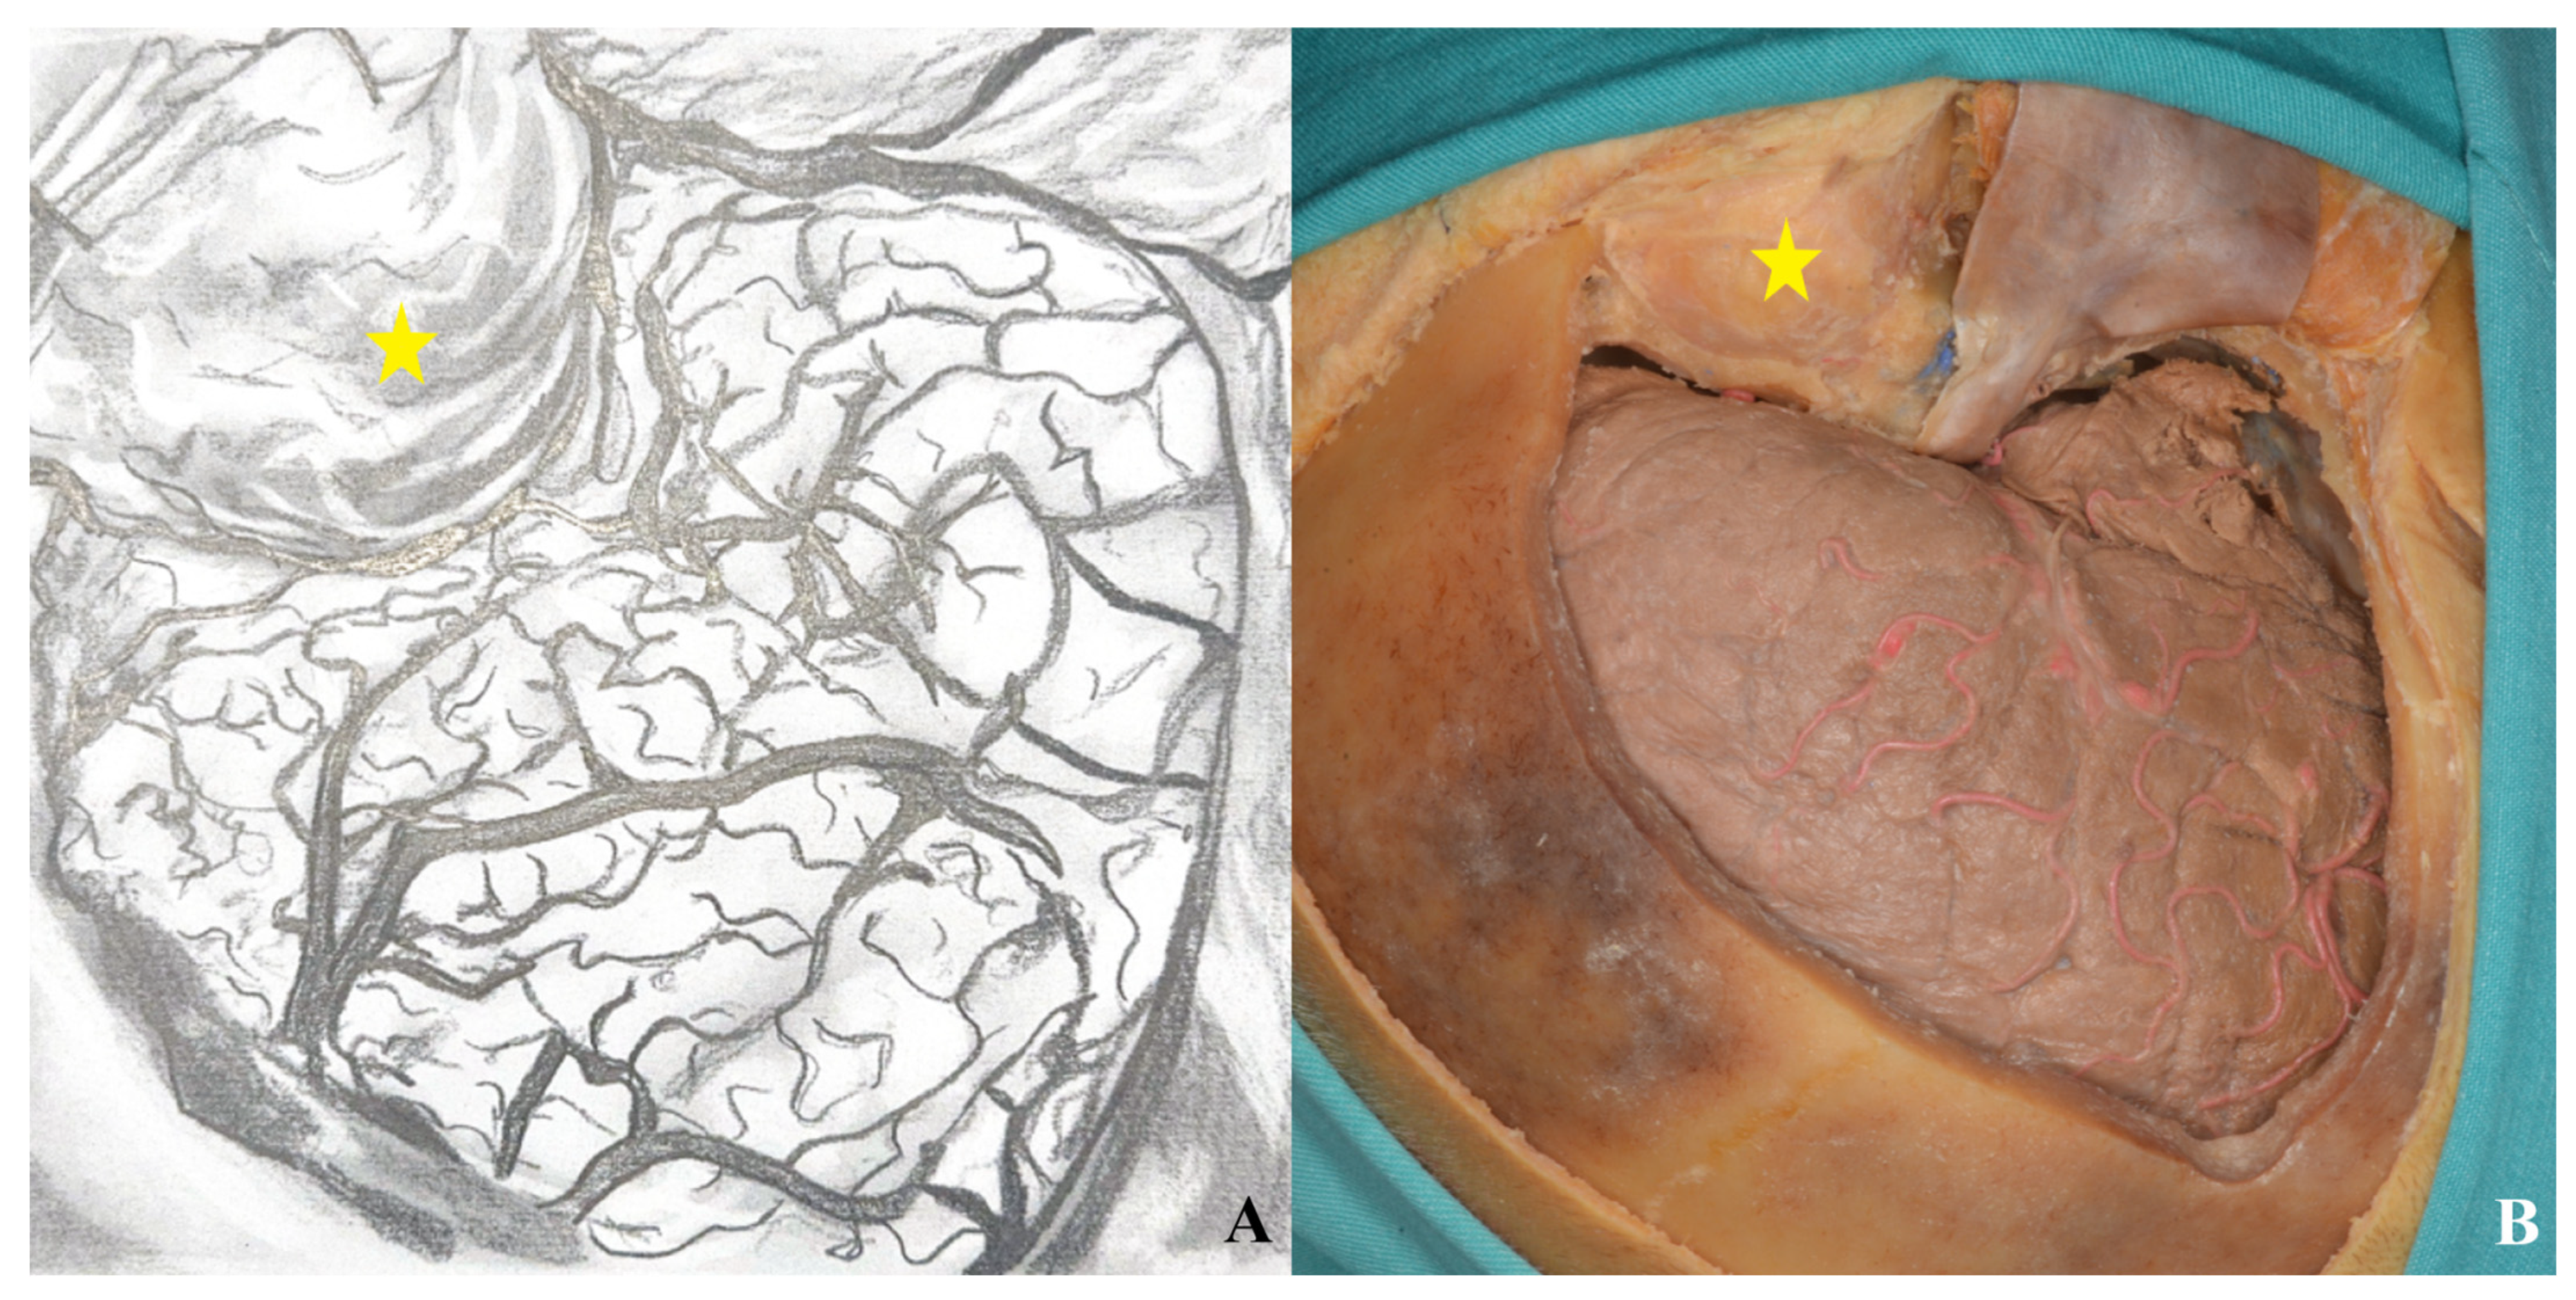

3.3. Lamina Terminalis

3.4. Lamina Terminalis Cistern